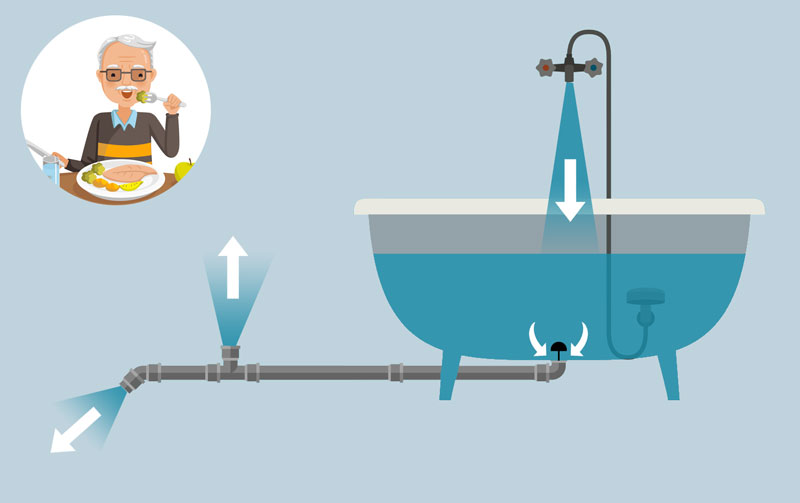

Chez une personne saine qui n’a pas mangé depuis un certain temps (après une bonne nuit de sommeil par exemple), le niveau d’eau de la baignoire a tendance à diminuer parce qu’il y a toujours des fuites et que les cellules ont des besoins en sucres continus. Pour remédier à ce problème, l’organisme fabrique des sucres à partir des protéines qu’il a digérées ou qu’il peut trouver dans les muscles, mais aussi à partir des graisses qu’il a stockées auparavant. Et il les réinjecte dans la baignoire ! Le pommeau de douche se met en marche, le niveau de la baignoire remonte doucement jusqu’à sa limite optimale après quoi le pommeau s’arrête.

Chez les personnes diabétiques, le pommeau de douche ne s’arrête pas : il reste ouvert en permanence. C’est la raison qui explique pourquoi, à leur réveil, le niveau de la baignoire est trop élevé alors même qu’elles n’ont pas ouvert le robinet depuis plus de 10 heures !

Ce problème de baignoire toujours trop remplie pose des problèmes à court terme pour les personnes diabétiques (le risque de débordement peut se traduire par des malaises, des épisodes d’hyperglycémie) mais aussi à long terme, car la baignoire n’a pas été construite pour supporter un poids d’eau si élevé (les nerfs et les vaisseaux sanguins qui se dégradent peu à peu sont à l’origine de très nombreuses maladies).